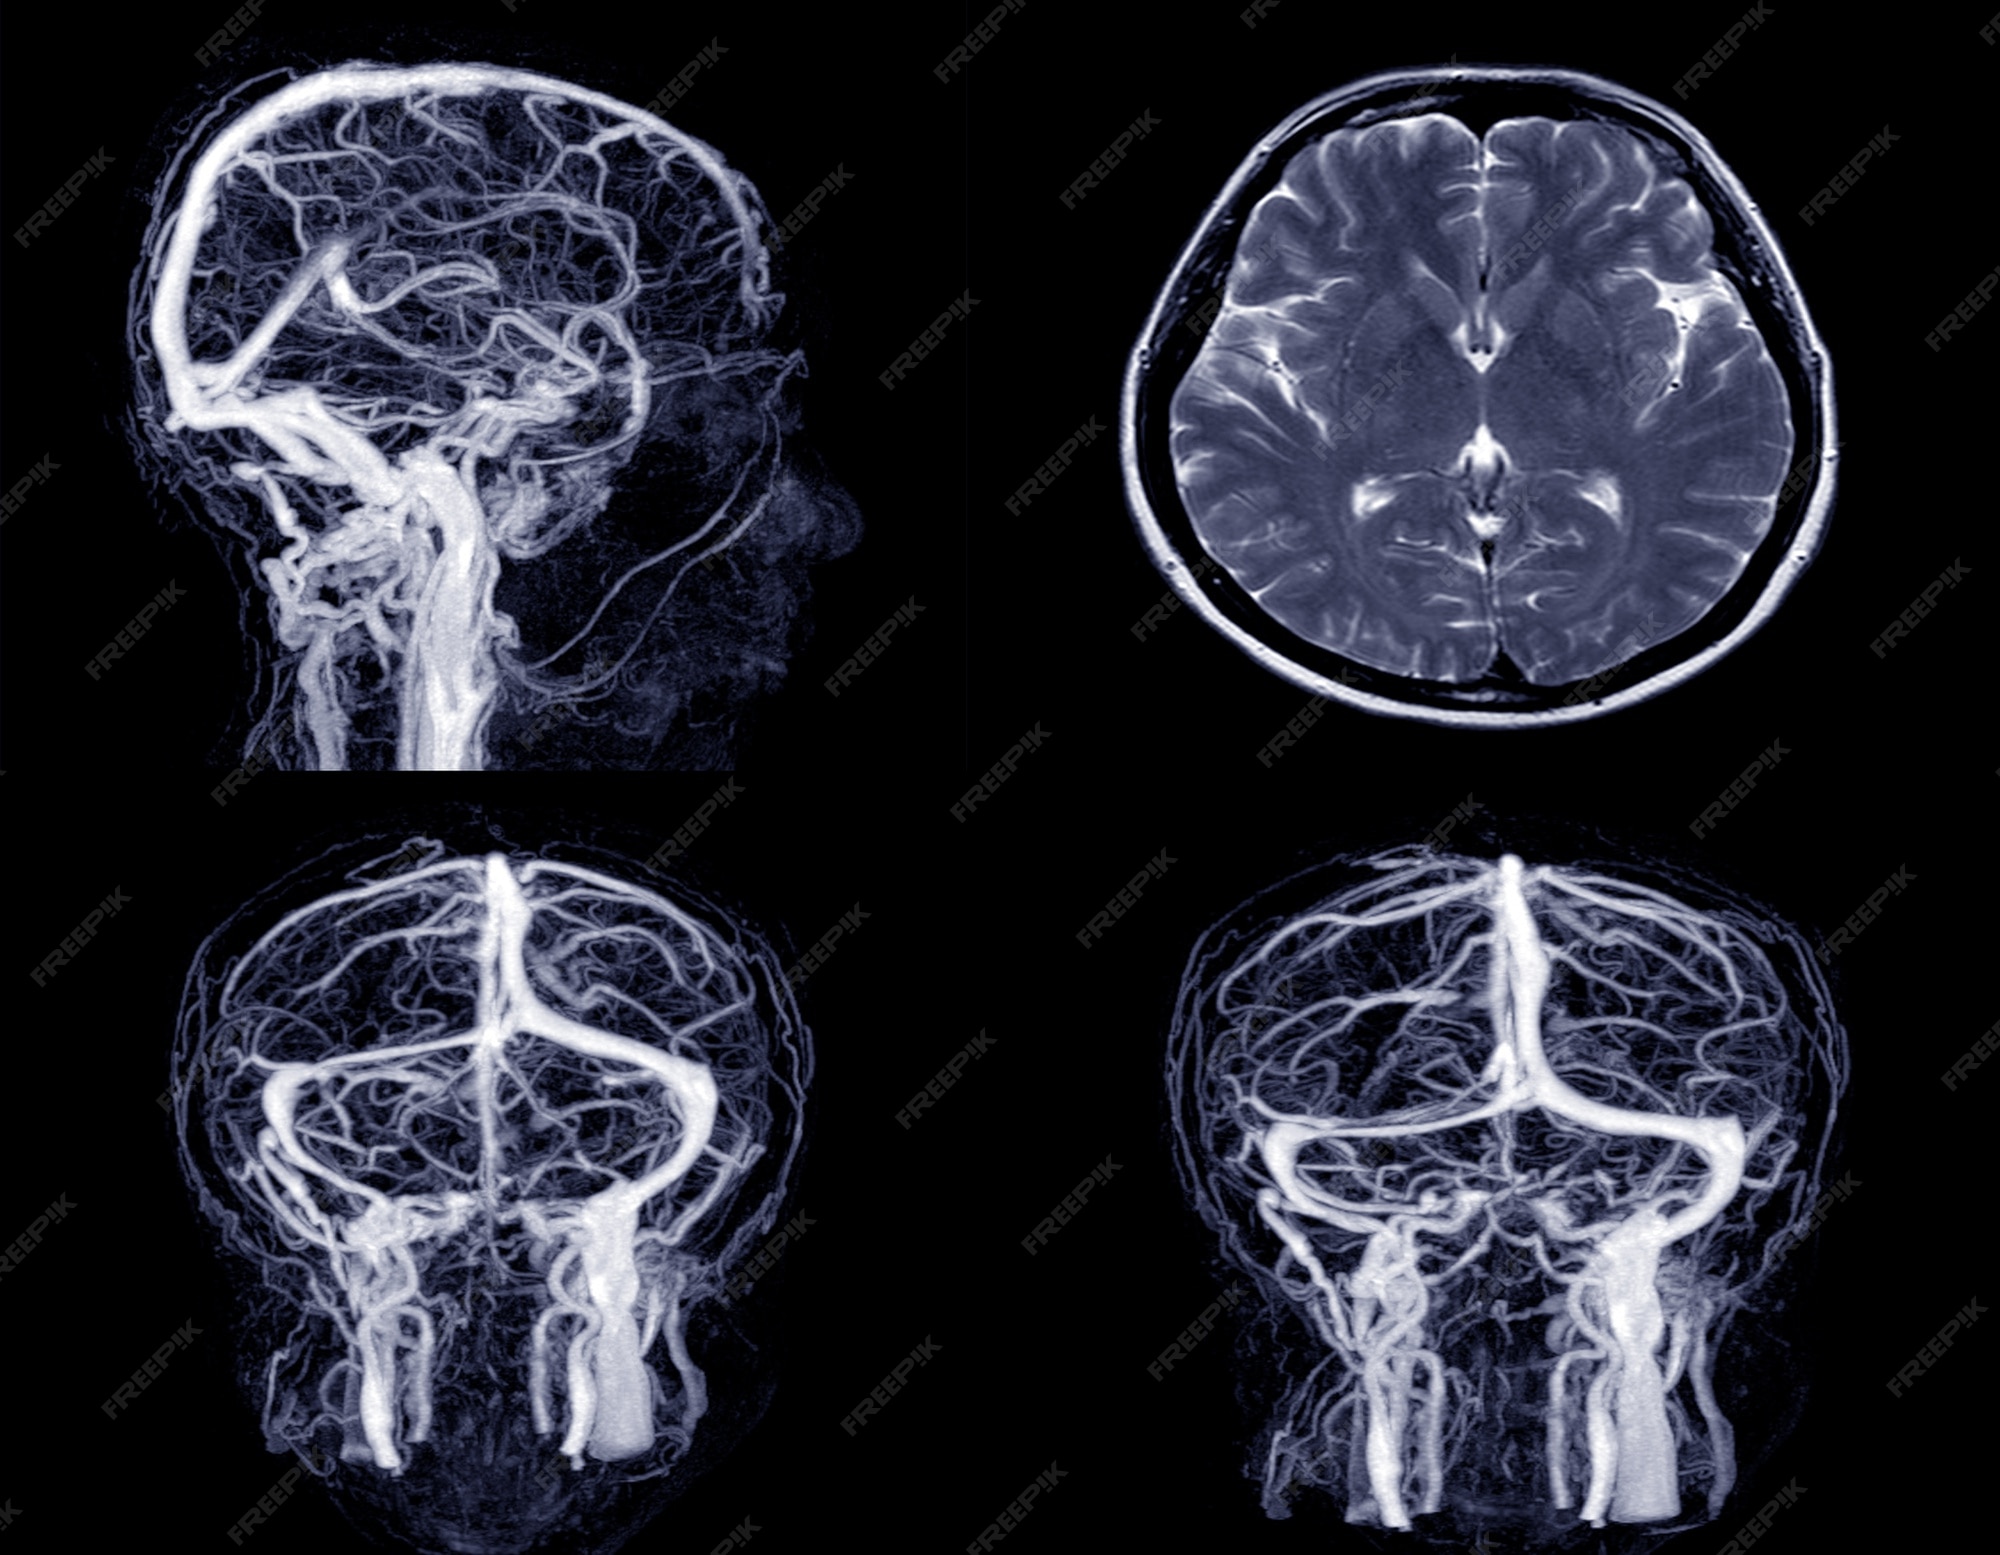

Premium Photo | Medical image MRV (magnetic resonance venography) Brain of veins in human head.

Discover how Magnetic Resonance Venography (MRV) of the brain provides detailed imaging of cerebral veins. Learn how this non-invasive diagnostic procedure detects blood clots, venous sinus thrombosis, and vascular abnormalities. Our expert guide explains the scan process, safety, and why it is essential for identifying neurological conditions caused by obstructed blood flow in the brain’s complex venous system.